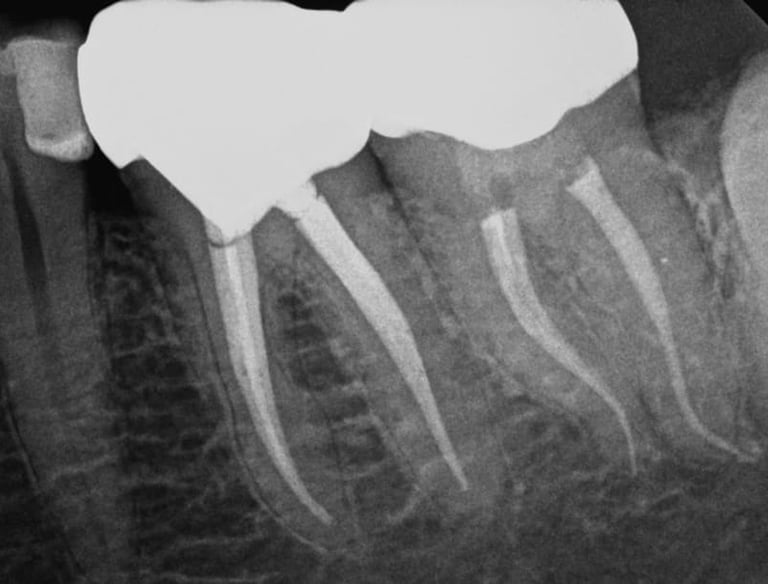

Cuando una caries profunda o un traumatismo alcanzan el nervio dental, es necesario realizar una endodoncia para conservar la pieza.

En IdenClinic eliminamos el tejido infectado del interior del diente y sellamos los conductos radiculares con máxima precisión, utilizando instrumentación rotatoria y control digital de longitud.

Este procedimiento detiene la infección, alivia el dolor y evita la extracción. Posteriormente, reforzamos el diente con una reconstrucción o corona protectora, devolviéndole su funcionalidad y aspecto natural para una salud bucal a largo plazo.

ENDODONCIA